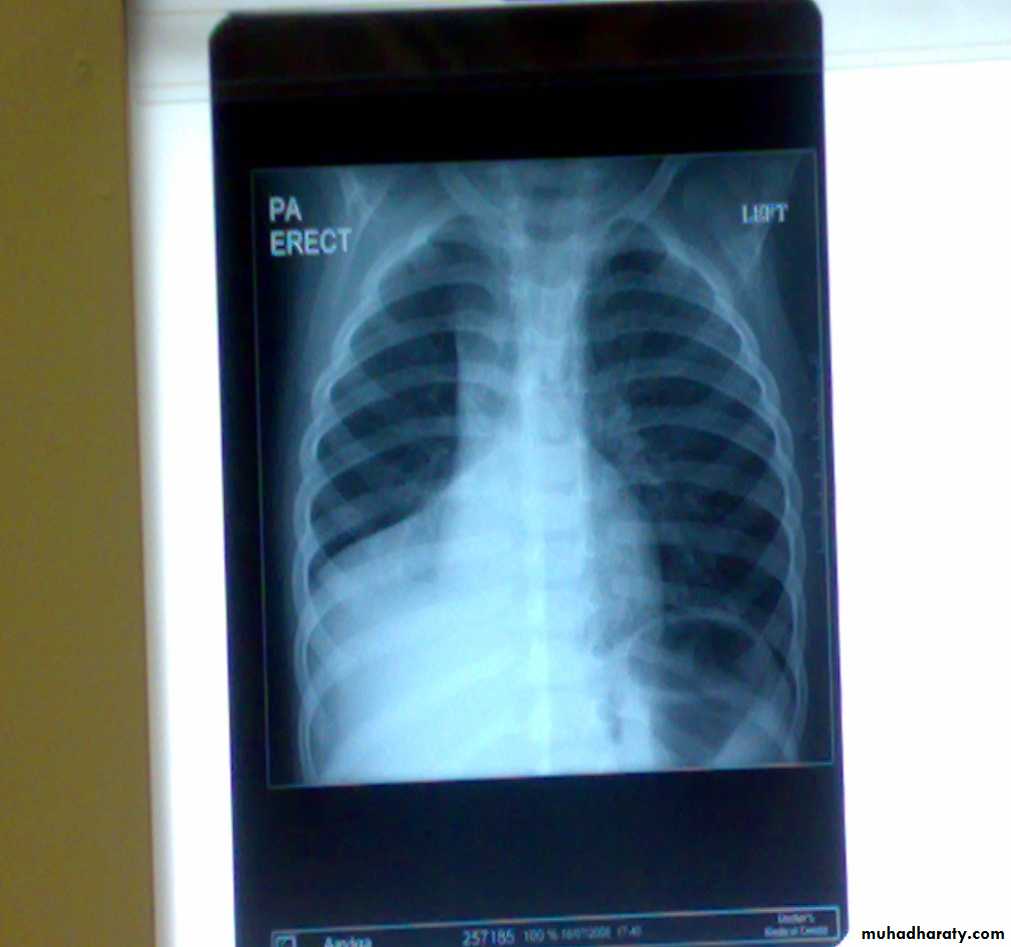

Foreign Body (RMB)